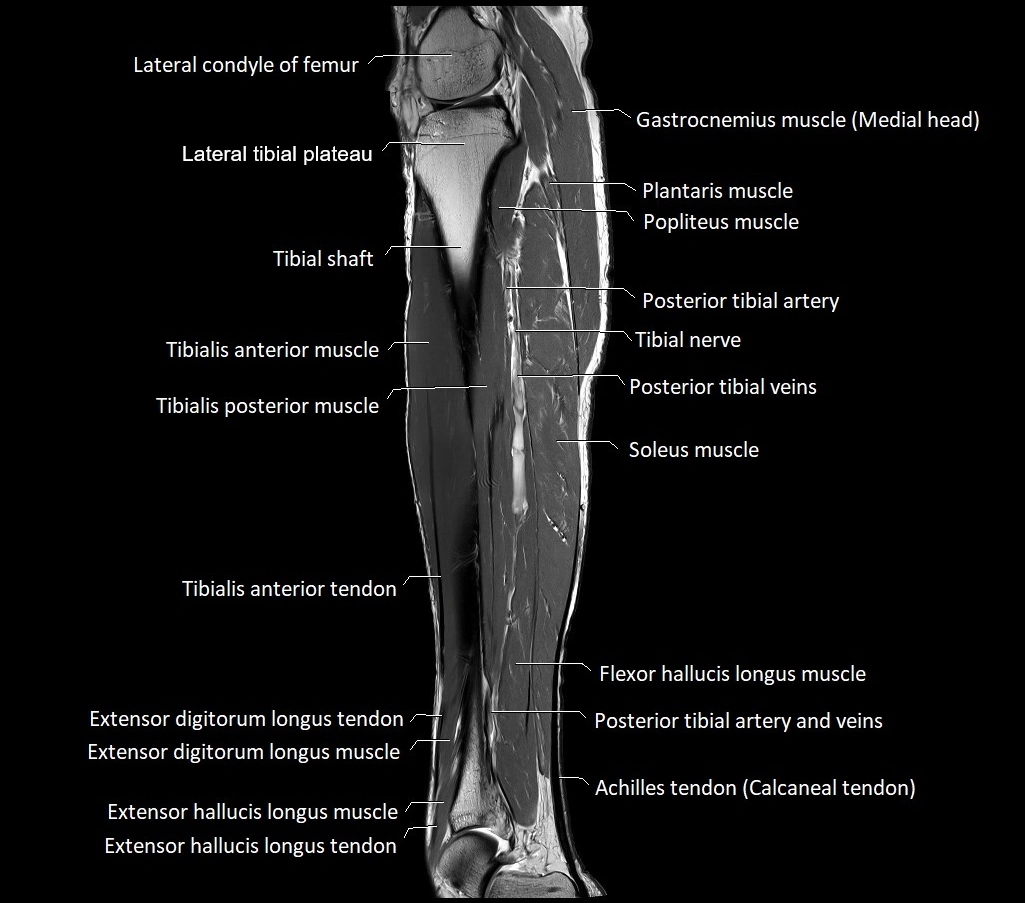

MRI image